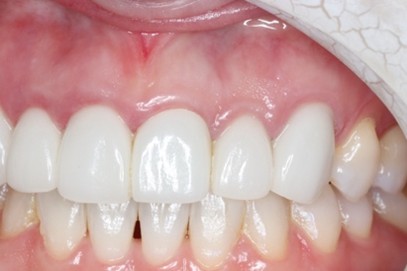

歯周病患者に対して前歯部に審美修復を行ったケースの症例紹介

Before

6前歯の被せ物の歯肉が赤く腫れており膿が出ている部分もあった。審美的とは言えない状況

After

セラミックセット後3年、歯肉の炎症はなく審美的な結果が得られている

他院でセラミック矯正を行ったがその後歯肉が腫れてしまい出血する様になった

初診時に入っていた被せ物は全て外し仮歯に置き換え、歯周基本治療を行った。その後歯肉の位置を調整して(クラウンレングスニング)仮歯を調整したのちにジルコニアセラミックを作成した。

審美修復に必要なことは、歯肉の健康だとつくづく感じている。いくら被せ物をセラミックで行ったところで土台である歯肉が健康でなければ本当の意味での審美修復は不可能であり長期的な予後が見込めない。まずは炎症のない口腔内の確立を第一に考える必要があると考える。